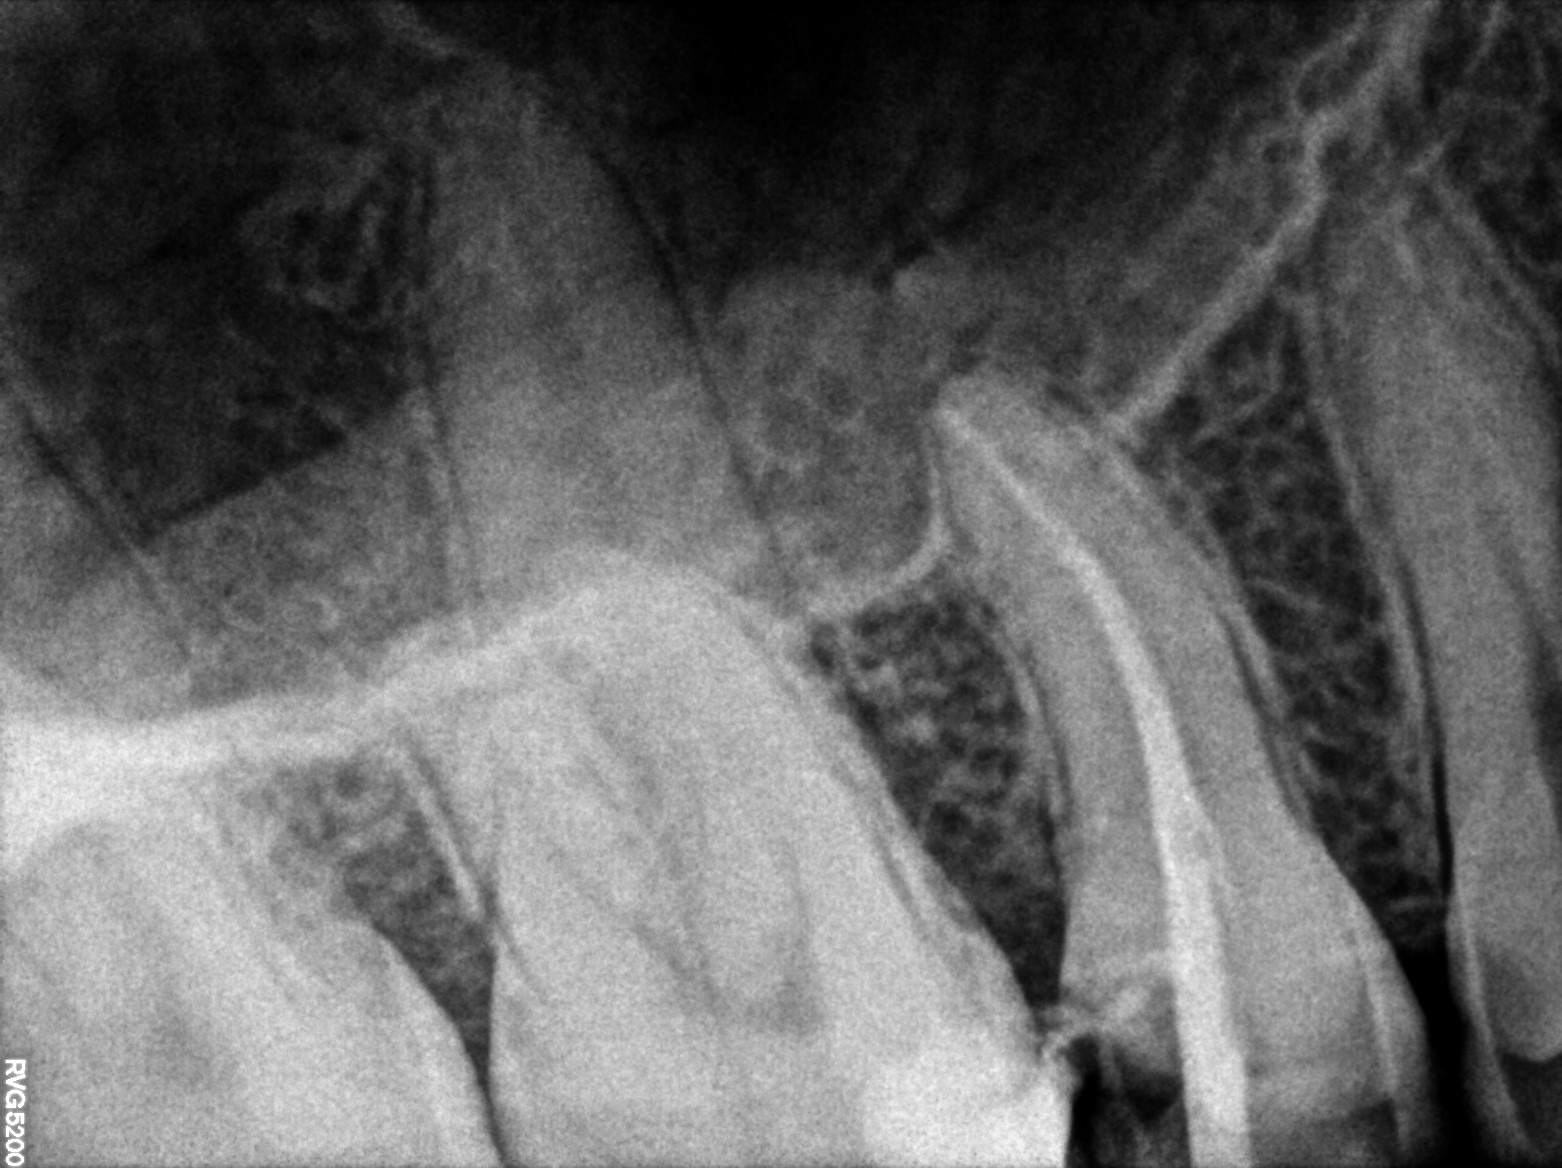

Dental Radiographs FHIR: DocumentReference · LOINC 24641-7

R55.jpg

24641-7